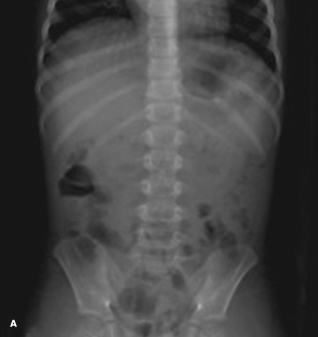

trichobezoars

La Donna J. Johnson, MD; Poonam Mahajan, MD

<p><img src="/sites/default/files/1206Con_PCTrichobez_A_0.jpg" width="85" height="90" style="float: left; margin: 5px;">For the second time in a week, a...